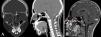

Medicina Clínica (English Edition) A rare cause of recurrent meningitis

A rare cause of recurrent meningitis

Una causa rara de meningitis recurrente